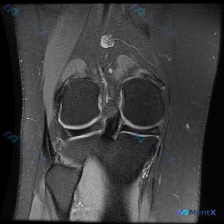

看到这个膝关节MRI的病例,整理了资料和分析思路分享给大家。 病例影像资料 这是一张膝关节冠状位MRI图像(考虑为质子密度加权像或T2加权像,对积液和软组织病变显示更敏感),影像所见核心信息如下: 1. 骨性结构:股骨远端、胫骨近端骨皮质完整,无明显骨折或骨质破坏,内外侧胫骨平台关节软骨下骨边界清晰...